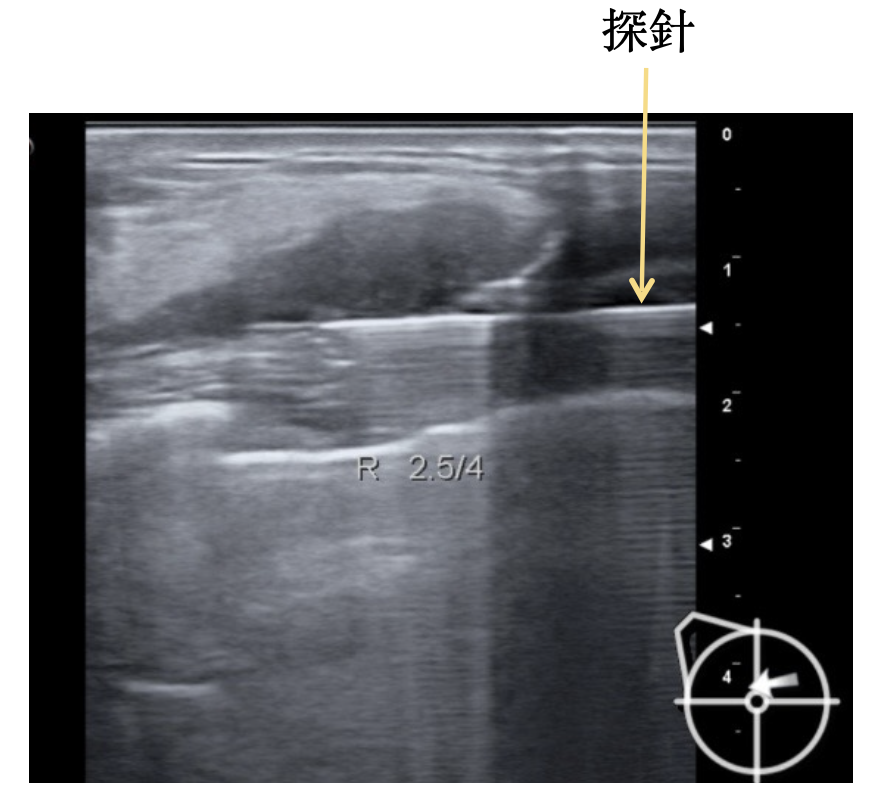

於乳房表皮劃開 0.3~0.5 公分切口,在超音波導引下插入探針,探針透過真空輔助,在超音波導引下取出(腫瘤)組織。

3. 超音波定位及引導之下,透過真空輔助抽吸取出腫瘤組織

透過後方檢體收集盒,保留高完整性的檢體